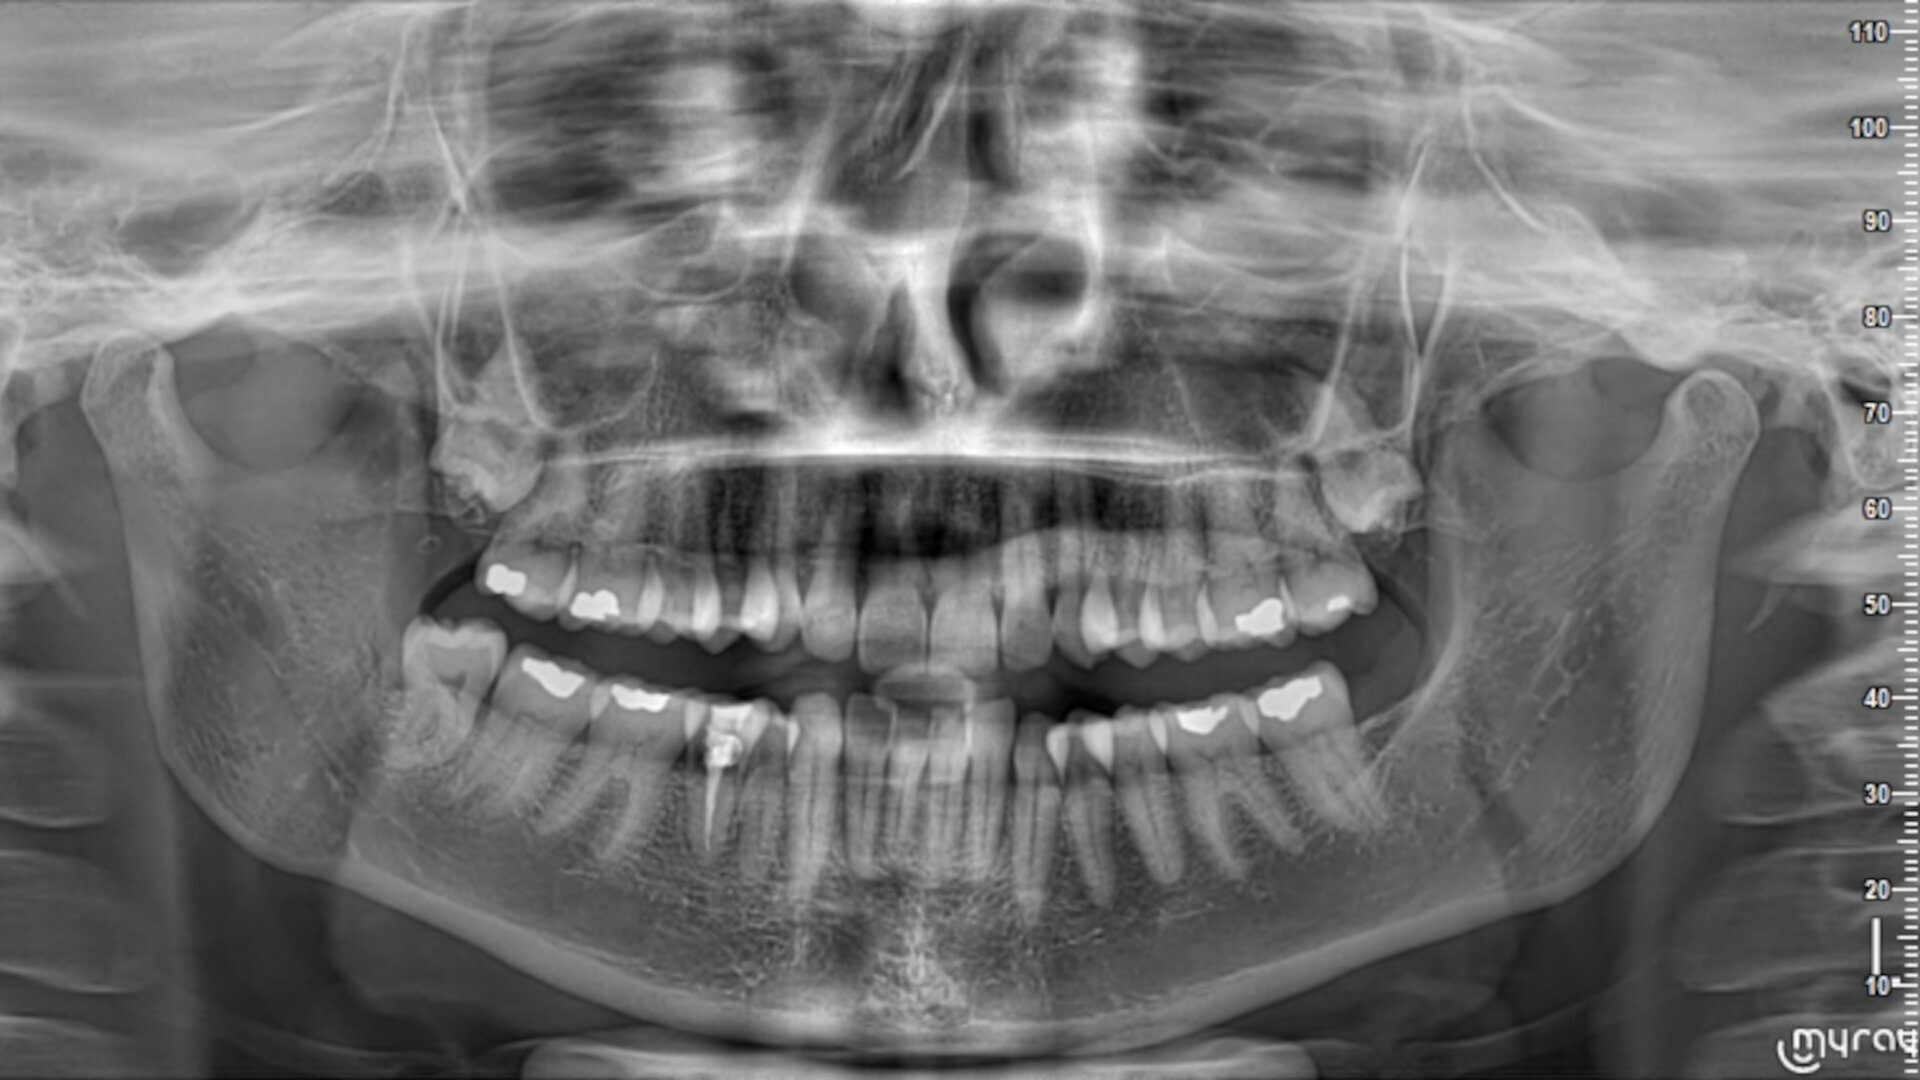

Fig. 2: Periapical radiograph of the initial situation.

The radiographic examination showed periapical radiolucency and a radiolucent lesion in the cervical area of the tooth (Figs. 1 & 2). To determine the extent and depth of the lesion, a CBCT scan was performed (Fig. 3). Based on the CBCT images and 3D reconstructions, a diagnosis of Heithersay Class III external cervical invasive root resorption (ECIR) was determined in an endodontically treated tooth with symptomatic periapical periodontitis. The patient was informed of the diagnosis, treatment plan alternatives and prognosis of the case.